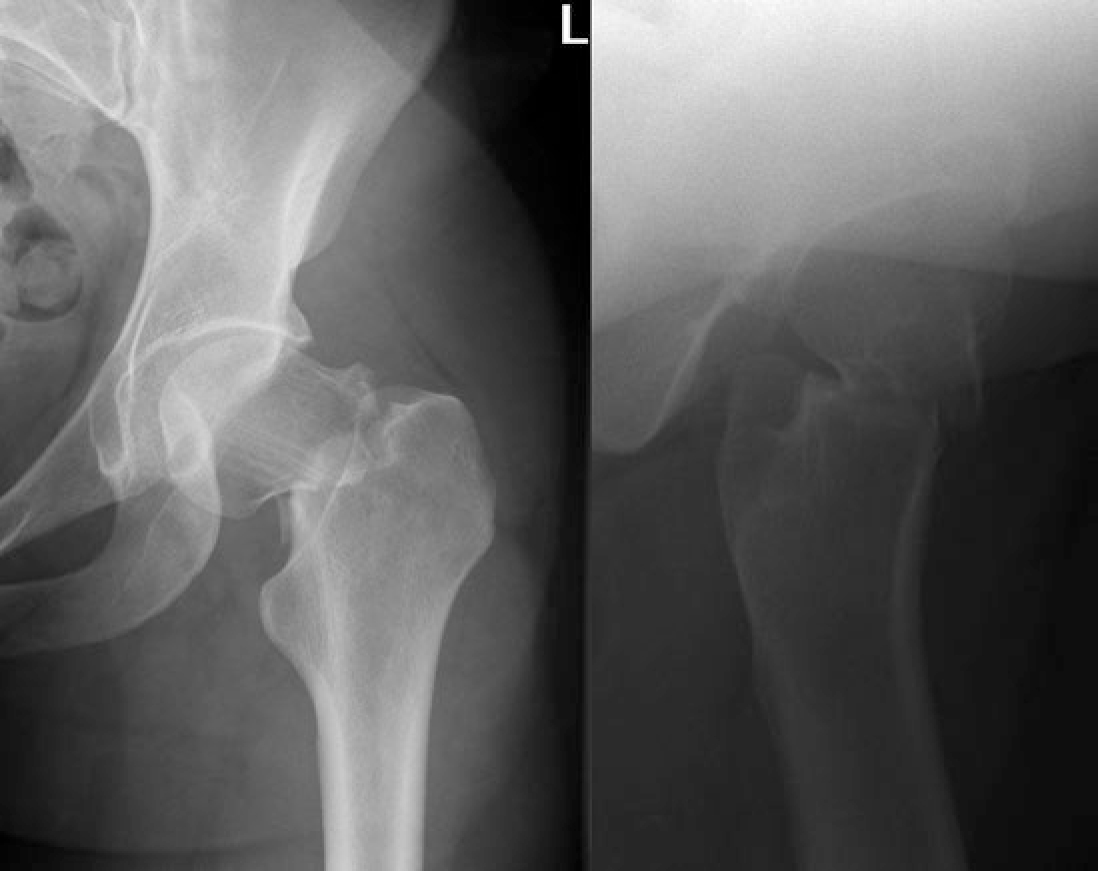

Een 28-jarige gezonde vrouw neemt deel aan de marathon van Rotterdam en krijgt na 38 kilometer plots pijn in haar linkerheup. Negenhonderd meter voor de finishlijn voelt ze ‘een knak’ en is ze niet meer in staat haar been te belasten. Ze bezoekt de medische post, waar de behandelend fysiotherapeut denkt aan een partiële spierruptuur. Vanwege de hevige pijn in de heup en het onvermogen het been te belasten, bezoekt de vrouw aansluitend de huisartsenpost. Ook de dienstdoende huisarts denkt aan een partiële spierruptuur en ze krijgt opiaten ter pijnstilling voorgeschreven. De volgende dag is de pijn onveranderd. Omdat de huisarts aan een totale spierruptuur denkt, verwijst hij de vrouw naar het ziekenhuis voor een echo van de spier. Echografie toont geen afwijkingen, maar de radioloog vindt de klachten zo ernstig dat hij een röntgenopname van de heup laat maken. Daarop wordt een gedisloceerde stressfractuur van de femurhals gediagnosticeerd [figuur].

Figuur | Röntgenopname toont een gedislokeerde stressfractuur van de femurhals